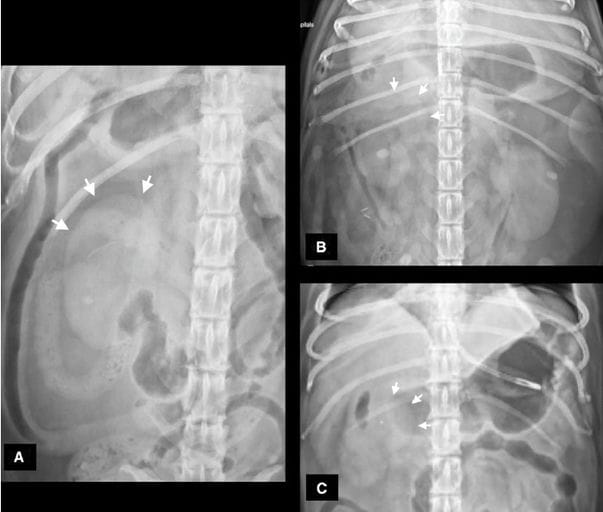

Ventrodorsal radiographs of three different dogs (A, B, C) with acute pancreatitis where .75% of the right renal margins, including the

cranial pole, are seen, and the renal “halo” sign was recorded as present.